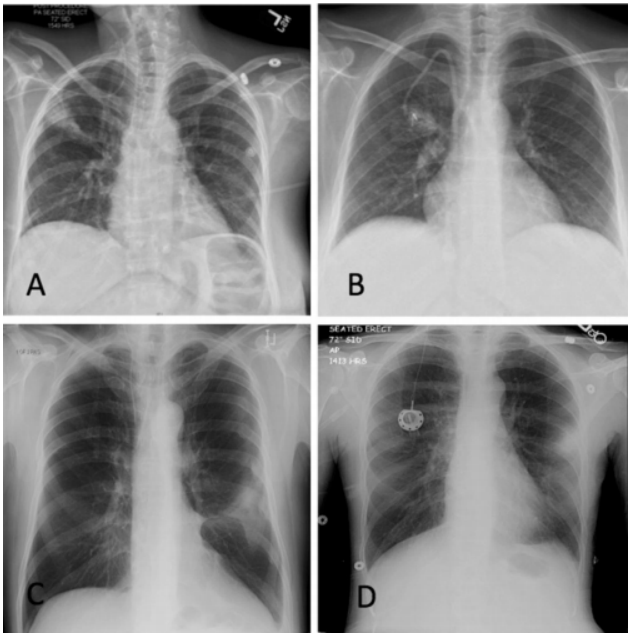

军团菌肺炎的影像学表现不具有特异性,实变是其常见的影像学发现,相对特异性的表现为磨玻璃影中混杂着边缘相对清晰的实变影,各个肺叶均可受累,1/3的病例可合并胸腔积液。免疫抑制患者的影像学表现同样不具有特异性。前述研究回顾性复习了某一癌症中心确诊的40例军团菌肺炎病例,其中,8例表现为单发或多发结节【6例实性伴有磨玻璃晕征或空洞,2例实性结节,边界清楚,没有磨玻璃晕或空洞;6例为1~2个大结节,1例双侧随机分布的大量小结节,1例局灶性磨玻璃影伴微小结节。所有CT均显示结节性浸润,仅有4例(50%)在胸部X线检查中显示结节性浸润】,32例表现为混合性非结节性肺异常(包括肺叶实变、磨玻璃影、斑片状浸润),2例发现肺炎旁胸腔积液。下图A为70岁女性,右肺上叶实性结节伴磨玻璃晕;B为41岁女性,右上肺叶有实心结节;C为17岁男性,右中叶结节伴中央空洞,伴磨玻璃晕;D为51岁女性,舌叶结节,中心空洞,周围磨玻璃晕;E为35岁女性,右下肺叶结节和周围的磨玻璃晕;F为7岁女性,舌叶结节,中央有空洞。也有一些患者偶然发现结节状军团菌肺部感染,症状不明显。我科确诊的一例军团菌肺炎患者,男性,66岁,“咳嗽咳痰伴发热2周”,每日游泳,可能与污染水接触有关,影像学以渗出样改变为主。治疗过程中出现实变、多发结节样改变。军团病的诊断需要借助于有效的检测手段。常用的检测方法包括常规培养、尿抗原检测、核酸检测。培养仍然是诊断军团菌肺炎的“金标准”,但该方法具有滞后性,可能会延误诊断。尿抗原是作为一线的诊断测试,能够快速诊断,使患者得到及时治疗。但尿抗原仅能检出嗜肺军团菌1组菌株,敏感性只有75%,容易导致部分患者被漏诊。核酸检测费用比较高,敏感性高达90%。二代测序能为诊断提供更有效、更快捷的手段。1988年,Cunha教授率先提出了WUH评分系统:①体温>39.4℃;②CRP>187 mg/L;③PLT<171×109/L(如正常下限为125×109/L,则建议PLT<200×109/L);④Na<133 ldh="">225 U/L(339 U/L);⑥干咳(包括不咳嗽、少痰,多痰排除)。【注:每项1分,3分可能诊断,4分可能极大,5分以上确诊】